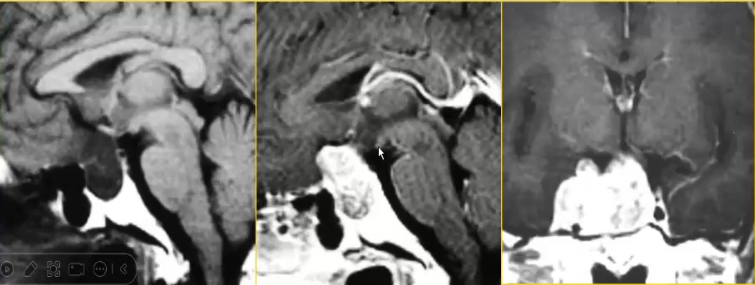

√男,52岁,头痛1年多,MRI发现右侧鞍旁肿瘤,T2WI呈非常高的亮信号,手术为海绵状血管瘤